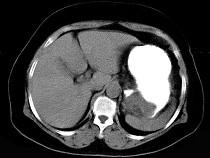

女43岁上腹不适多年,体检行CT扫描如图,最可能的诊断为()A.胃癌B.胃平滑肌瘤C.胃平滑肌肉瘤D.胃淋巴瘤E.胃蛔虫团块

问题 女43岁上腹不适多年,体检行CT扫描如图,最可能的诊断为()

选项 A.胃癌 B.胃平滑肌瘤 C.胃平滑肌肉瘤 D.胃淋巴瘤 E.胃蛔虫团块

答案 B